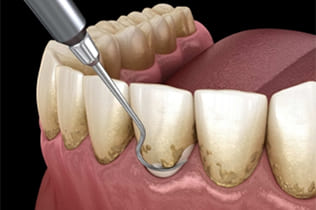

STEP 2

- クリーニング

- 手術前にクリーニングを行います。

- 手術の成功のため、手術前にはお口全体のクリーニング(歯石取り等)をお願い致しております。